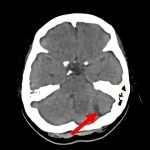

断層撮影